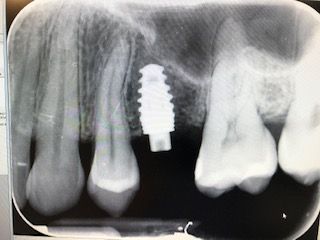

• Odbudowy na implantach Straumann i Neodent.

Został mi wybity ząb górna jedynka. Na chwilę obecną mam protezę. Nie czuję się z nią dobrze. Jakie może być inne rozwiązanie?

Oczywiście, rozwiązaniem tego problemu może być wszczepienie implantu, który jest zastępstwem dla naturalnego korzenia. Po wygojeniu na wszczepiony implant prosto mówiąc mocuje się koronę, która niczym nie odbiega od wyglądu naturalnego zęba.